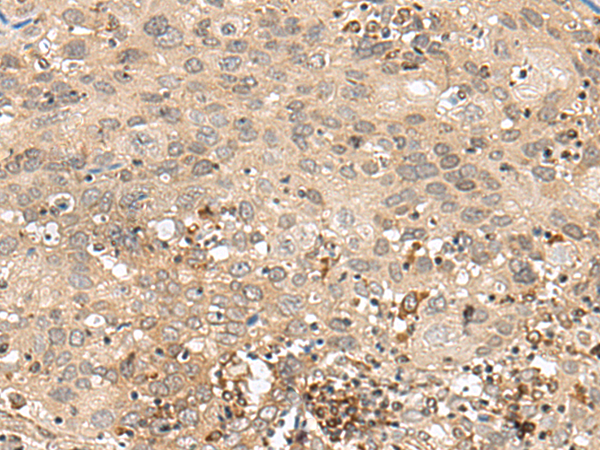

分类: 科研抗体货号: P13458别名: SCN2; GFI-1; GFI1A; ZNF163应用: IHC反应种属: Human, Mouse, Rat